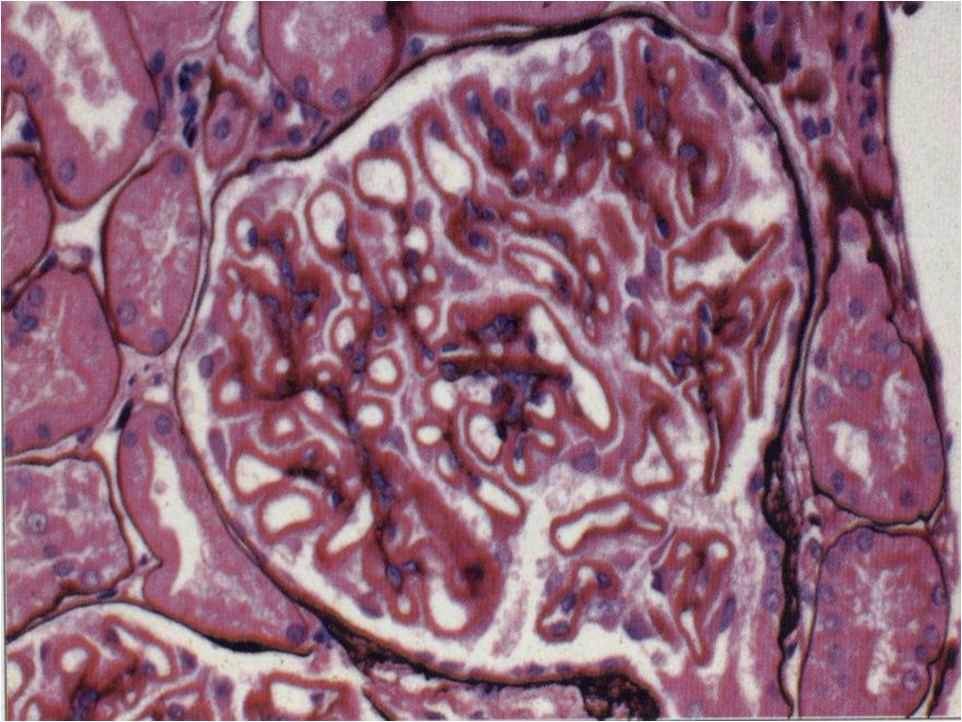

(四)膜性肾病

光镜下可见肾小球弥漫性病变,早期仅于肾小球基底膜上皮侧见多数排列整齐的嗜复红小颗粒(Masson染色);进而有钉突形成(嗜银染色),基底膜逐渐增厚。免疫病理显示IgG和C3呈细颗粒状沿肾小球毛细血管壁沉积。电镜下早期可见GBM上皮侧有排列整齐的电子致密物,常伴有广泛足突融合(图5-4-4)。 本病男性多于女性,好发于中老年。通常起病隐匿,约80%表现为NS,约30%可伴有镜下血尿,一般无肉眼血尿。常在发病5~10年后逐渐出现肾功能损害。本病极易发生血栓栓塞并发症,肾静脉血栓发生率可高达40%~50%。

膜性肾病约占我国原发性NS的20%。约有20%~35%患者的临床表现可自发缓解。约60%~70%的早期膜性肾病患者(尚未出现钉突)经糖皮质激素和细胞毒药物治疗后可达临床缓解。但随疾病逐渐进展,病理变化加重,治疗疗效则较差。本病变多呈缓慢进展,我国、日本和我国香港特区的研究显示,10年肾脏存活率为80%~90%,明显较西方国家预后好。